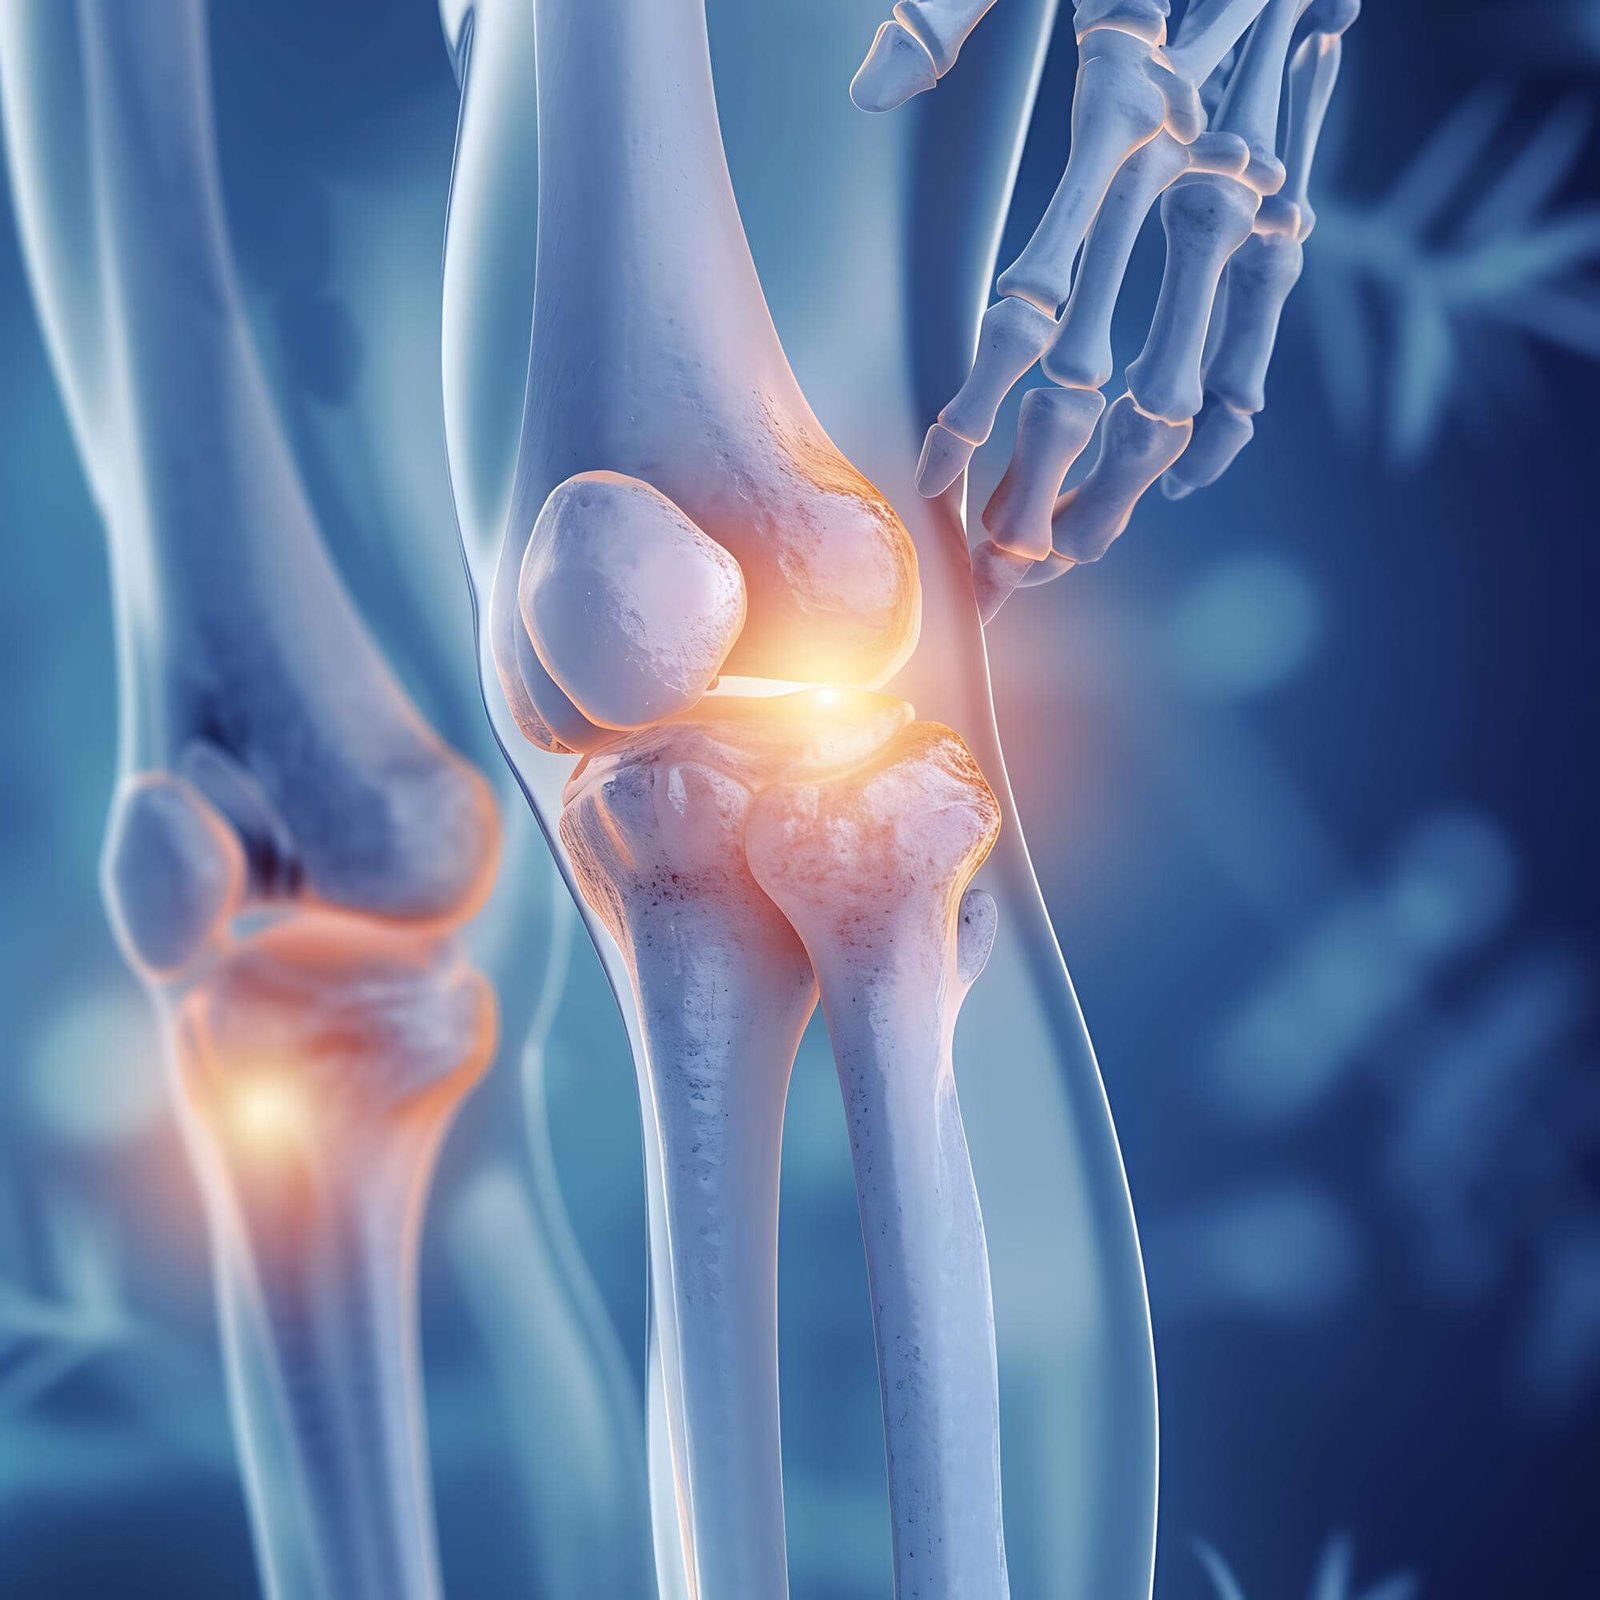

Knee Arthroscopy Surgery

Minimally invasive knee arthroscopy surgery for injuries and Ligament Tear ( ACL, PCL, MCL, LCL), Meniscus Tear, Cartilage Loss ensuring precision treatment, faster recovery, and improved joint function.

Knee Replacement Surgery

Expert knee replacement surgery in Ahmedabad, using Modern Implants and Precision and Pain free Techniques to restore mobility, reduce pain, and improve quality of life.